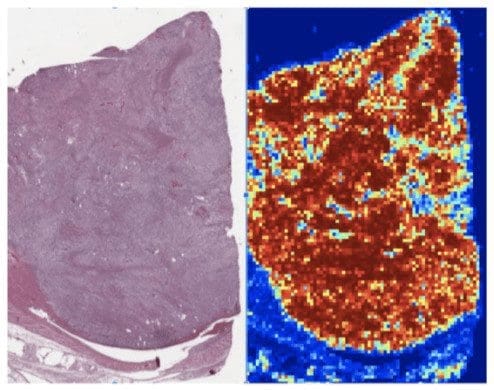

In terms of WSI analysis, explainable AI will act as a support system that scans image sectors and highlights regions of interest with suspicious cellular structures. The machine won’t make any decision, but will speed up the process and make the work of a doctor easier. This is possible because WSI is more accurate and quicker in terms of image scanning, giving less chance to omit specific regions. Here is an example of renal clear cell carcinoma on the low resolution WSI.

Kidney renal clear cell carcinoma is predicted to be high risk (left), with the AI-predicted “risk heatmap” on the right; red patches correspond to “high-risk” and blue patches to “low-risk”.

As you can see on the image on the right, the AI support system highlights the regions of high risk where cancer cells are more likely to be. This eliminates the need to physically analyze the whole image of a kidney, providing hints for medical expertise and attention. Similar heatmaps are used for even closer and more high resolution analysis of kidney tissue.